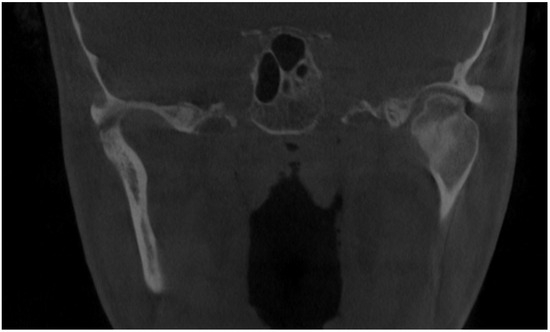

Figure 1.

Initial scan—CBCT, coronal view—enlargement and overgrowth of left condylar head causing visible mandibular and skeletal asymmetry. The patient underwent orthodontic treatment (2006–2010) and scheduled BSSO (bilateral sagittal split osteotomy) for surgical correction of the asymmetrical mandibular and featured dentofacial deformity. Six years after the procedure, the patient demonstrated signs of re-occurrence of mandibular asymmetry. After some corrective orthodontic approaches, consultations, and treatment proposals, the patient was scheduled for consultation in our ward (2021–2022). Because of severe mandibular asymmetry, unilateral open bite, chin deviation, midline shift towards the healthy right side, enlargement and overgrowth of the left mandibular basis and ramus, a suspicion of condylar hyperplasia was raised [1,2]. Because the CBCT scans revealed overall extensive progressive growth of the left condylar head, a decision for additional SPECT was decided. According to the known literature, a one-sided open bite with chin deviation towards the heathy opposite side, followed by mandibular corpus enlargement and elongation, are quite common clinical syndromes of condylar hyperplasia. The scope of visible changes in mandibular anatomy is greatly dependent on the time of this abnormal pathological growth and its intensity. It is quite important to evaluate each patient individually because mandibular abnormal growth might not only lead to dentoalveolar changes but also skeletal changes, which, depending on their intensity, might require some degree of surgical intervention. Rarely, condylar hyperplasia might present itself as an osteochondroma or other rare temporomandibular joint tumors [1,2,3]. Therefore, each case of asymmetry, bone change, visible bone enlargement, and overgrowth should be carefully evaluated. Abbreviations: CBCT—cone beam computed tomography, SPECT—single-photon emission computed tomography.